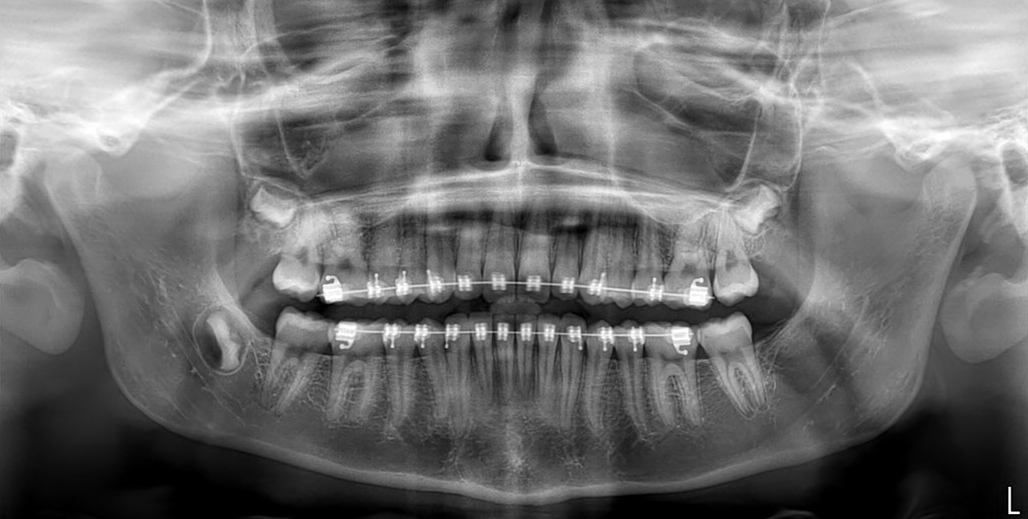

Panorámica

Es un examen dental con rayos X bidimensionales (2D) que captura imágenes de la boca entera en una sola toma, incluyendo los dientes, las mandíbulas inferior y superior, y las estructuras y los tejidos que las rodean. Es la prueba radiológica más común. Permite detectar caries y periodontitis, ver muelas de juicio y dientes emergentes, planear tratamientos de ortodoncia, entre otros.